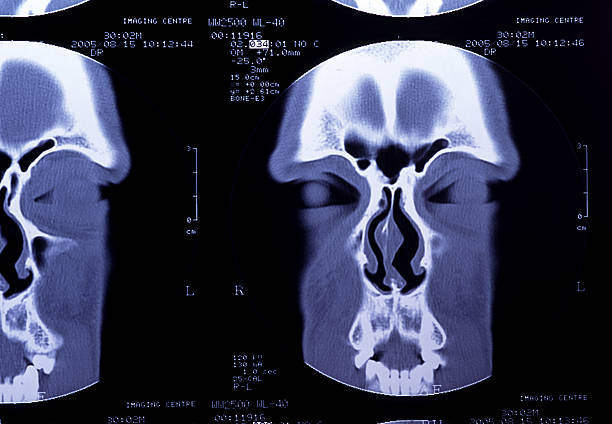

A CT scan, sometimes called a CAT scan, uses a special X-ray machine and computer technology to take multiple images for a detailed or “layered” look at the sinuses.

Unlike traditional CT scanners, our scanner is specifically designed to take images only of the sinuses and temporal bones. Focusing on these areas allows us to deliver a superior image without using a full-body scanner.